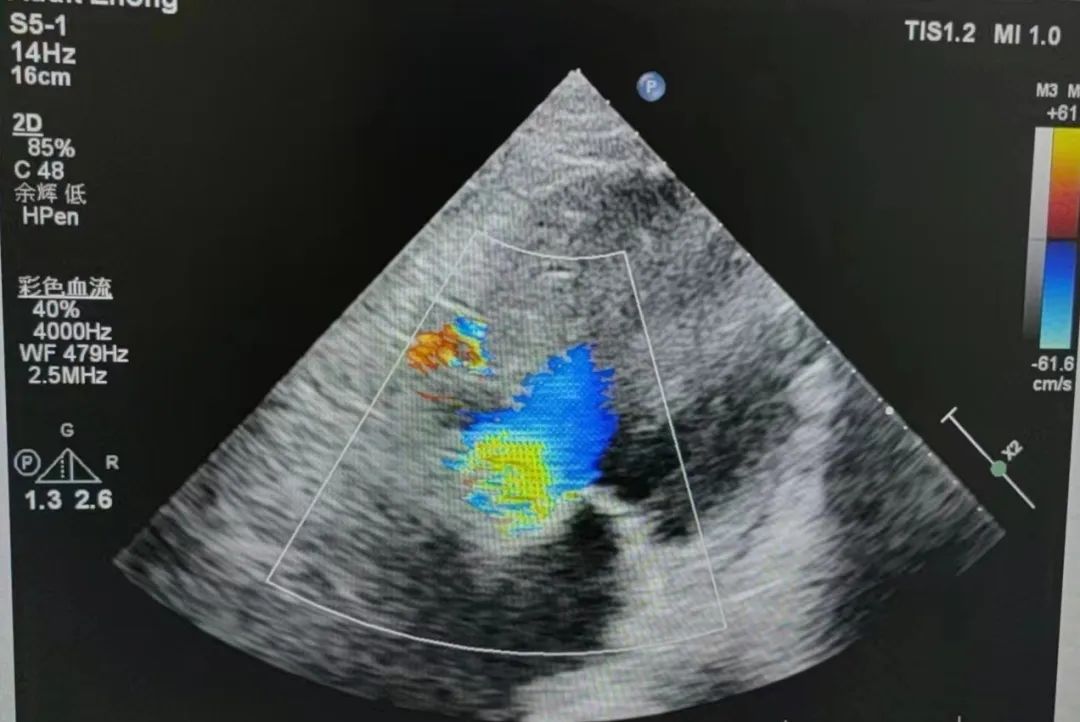

2、病史:患者于2月前反复于活动后出现气促,伴阵发性咳嗽,爬2层楼梯时即出现,休息后可缓解,无胸闷痛,无心悸,无咳粉红色泡沫痰,无恶心呕吐,遂至当地医院就诊,予对症处理后症状可改善(具体不详)。2周前,患者再次出现上述症状,性质同前,遂至我院就诊,完善心脏彩超提示AS(重度)合并AI(重度),抽血BNP:1897.30pg/ml,现患者为求进一步诊治来我院,门诊考虑"心脏瓣膜病"收入我科。

4、辅助检查:心脏彩超提示AS(重度)合并AI(重度),抽血BNP:1897.30pg/ml。

术后无瓣周漏

平均压差降为9mmHg平均流速降为1.41m/s

瓣膜释放后行血流动力学评估,跨瓣压差从术前100mmHg降至9mmHg,无瓣周漏,左冠脉灌注良好,手术圆满完成。